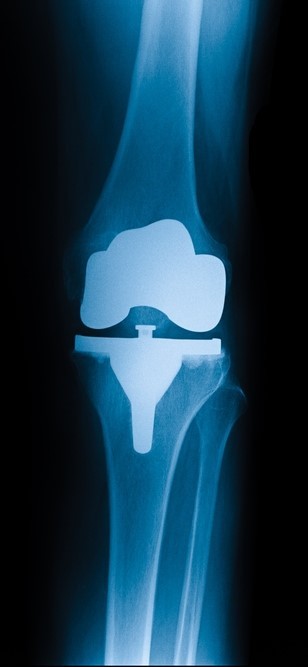

Knee Replacement Surgery is also known as Arthroplasty. This surgery is recommended when there is any structural damage to the knee due to wear and tear or in case of osteoarthritis or rheumatoid arthritis. In a Knee Replacement Surgery, the knee joint or the adjoining parts are partially or completely replaced with prosthetics.

Total Knee Replacement Surgery

Partial Knee Replacement Surgery

Knee Cap Replacement Surgery

Revision Knee Replacement Surgery